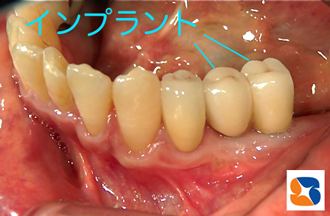

インプラント治療が始まってから4ヶ月。インプラント周囲の歯茎を、ぶ厚くて丈夫な質のものに変えました。あとは、型取りをして、完成を待つのみです。

完成されたインプラントの周囲歯肉は、ブラシ圧に十分耐えれるだけの強い体質になりました。これで日々のプラークコントロールもOK ! いつまでも永く使っていただけるはずです。